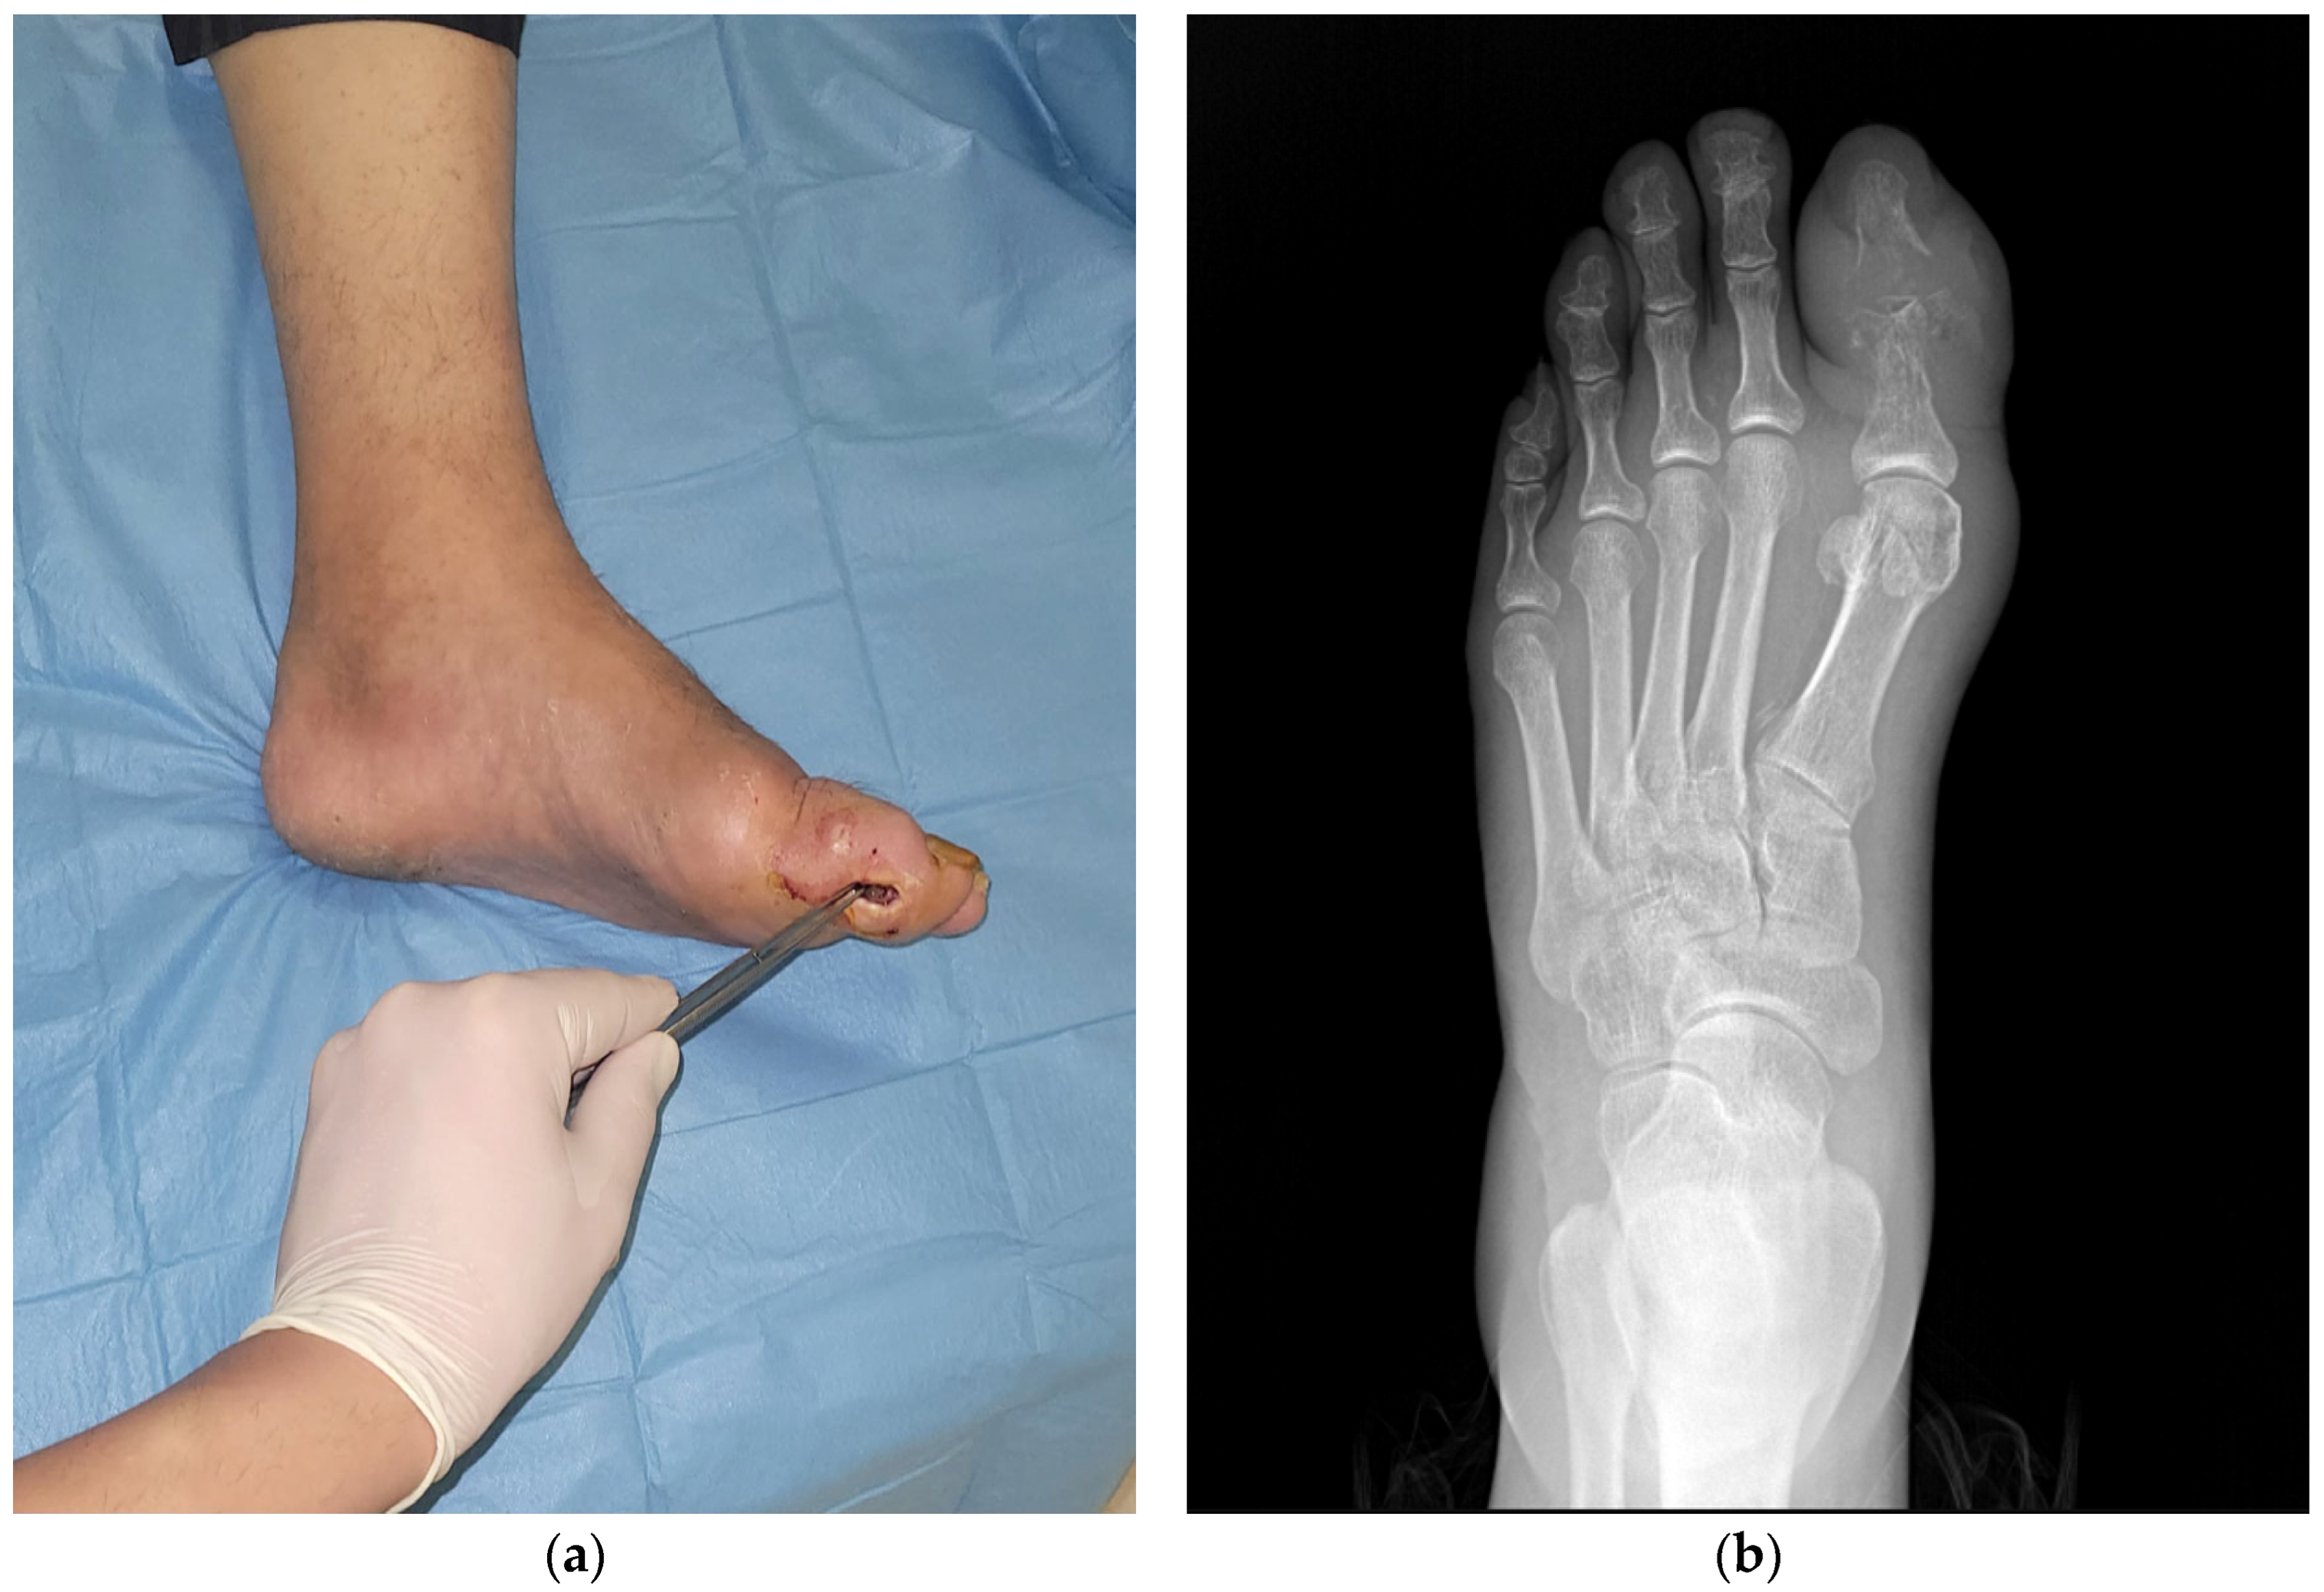

- Positive probe-to-bone (PTB) test (defined as palpable bone through the ulcer using a sterile blunt metal probe);

- Underwent surgical intervention (debridement or amputation) during which deep tissue and bone culture samples were intended to be collected simultaneously;

2.3. Specimen Collection